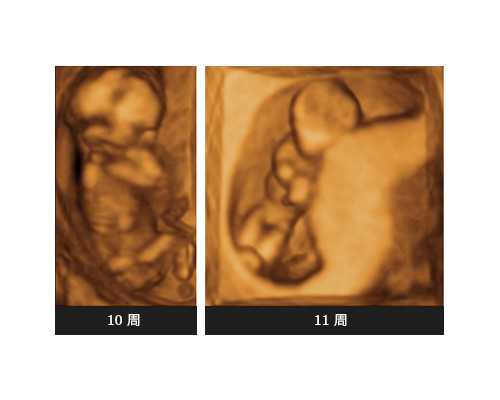

第1步,要确认怀孕,并且有胎心胎芽。

第2步,确认怀孕周期:孕7周,胎芽长度达到10mm或以上。

第1步,必须胎龄满7周以上,或者胚芽10MM以上,这个在前面有提到过。

4.B超证明怀孕足7-8周以上.胚芽达10MM(7周)至16.3MM(8周)以上就可鉴定.

这种检验胎儿性别的方法对于准妈妈们来说只需要在B超检验报告中显示实际怀孕周期达到第七周,胎儿的胚芽长度达到10MM以上即可。检验所需的材料也只是对准妈妈的手臂静脉血进行采样,这种程度仅仅相当于在医院进行体检的时候进行的抽血化验,所以对于孕妈和腹中的胎儿是不存在任何的威胁的,不会造成任何的伤害。完全值得家长朋友们放心和信赖。

2、确认宝宝满7周,胚芽长度达10mm或以上。

(1)B超确定婴儿满7周或以上,胚芽长度达到10mm或以上。